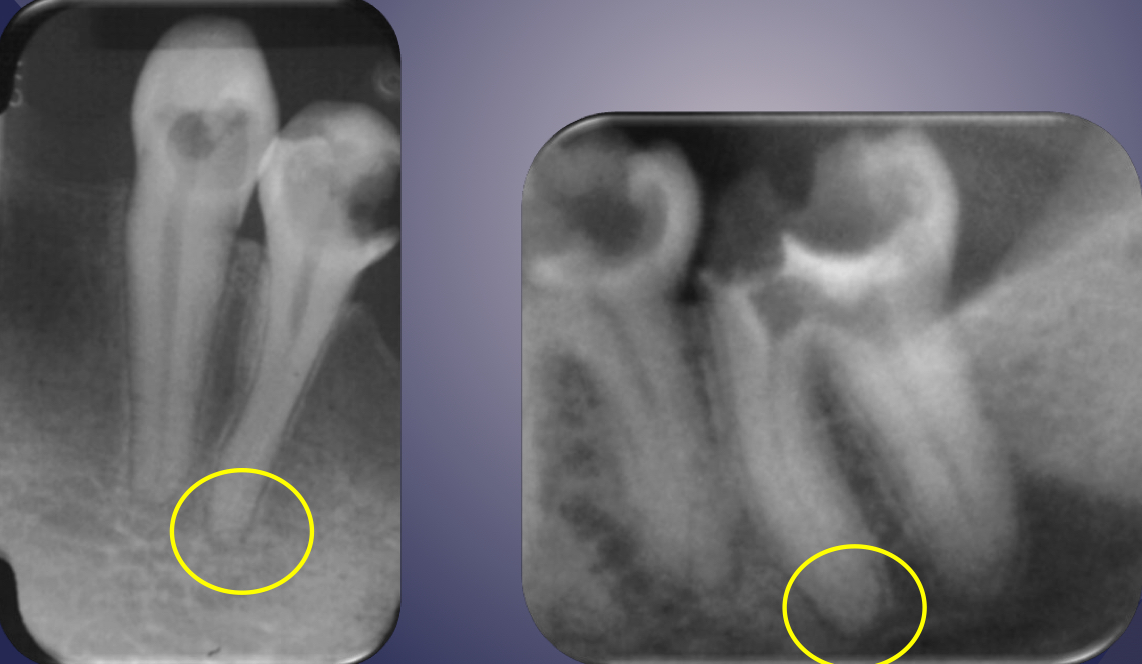

radiographic signs:

widened PDL space

loss of lamina dura

apical periodontitis

lack of continuous lamina dura, initial signÂ

apical periodontitisÂ

rarefaction

loss of bone mineral

osteitis

bone inflammation

rarefaction + osteitis = ?

increased radiolucency

loss of bone mineral + osteitis = increased radiolucency

rarefying osteitis

rarefying osteitis (LD gone and radiolucency)

chronic inflam with a non-vital toothÂ

radiolucent due to removal of bone

sequelae of acute episodeÂ

includes abscess, granuloma, or radicular cyst (these three have no distinction radiologically)

early periapical lesion

widening of PDL space, thickening of LD